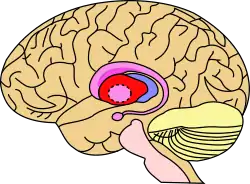

![]() Putamen (in red) shown within the brain | |

The putamen (/pjutˈeɪmən/; from Latin, meaning "nutshell") is a round structure located at the base of the forebrain (telencephalon). The putamen and caudate nucleus together form the dorsal striatum. It is also one of the structures that compose the basal nuclei. Through various pathways, the putamen is connected to the substantia nigra, the globus pallidus, the claustrum, and the thalamus, in addition to many regions of the cerebral cortex. A primary function of the putamen is to regulate movements at various stages (e.g. preparation and execution) and influence various types of learning. It employs GABA, acetylcholine, and enkephalin to perform its functions. The putamen also plays a role in degenerative neurological disorders, such as Parkinson's disease.

The putamen is a structure in the forebrain. Along with the caudate nucleus it forms the dorsal striatum. The caudate and putamen contain the same types of neurons and circuits – many neuroanatomists consider the dorsal striatum to be a single structure, divided into two parts by a large fiber tract, the internal capsule, passing through the middle. The putamen, together with the globus pallidus, makes up the lentiform nucleus. The putamen is the outermost portion of the basal ganglia. These are a group of nuclei in the brain that are interconnected with the cerebral cortex, thalamus, and brainstem. Basal ganglia include the dorsal striatum, substantia nigra, nucleus accumbens, and the subthalamic nucleus.